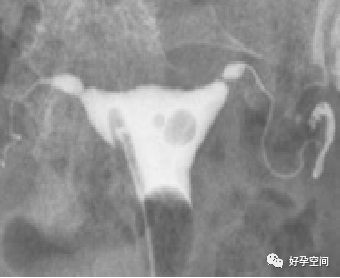

6、正常宫角:正常宫角有尖形、绞窄形、钝形和圆钝形四种形态。

尖形宫角

绞窄形宫角

钝形宫角

圆钝形宫角